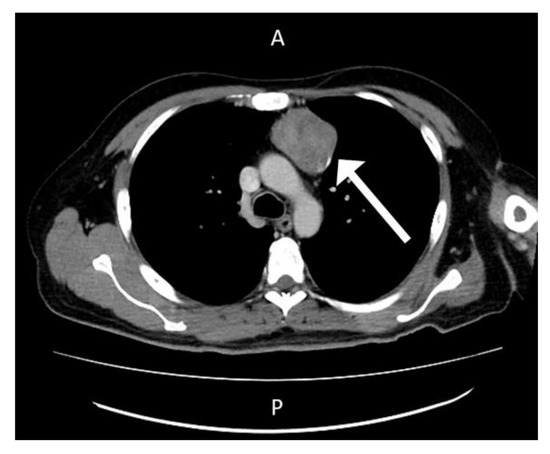

Background and Objectives: Thymomas are associated with a high frequency of paraneoplastic manifestations. Paraneoplastic syndrome (PNS) with thymoma presents a challenge to clinicians because of the need to decipher the association between the presenting symptoms and the underlying tumor. The condition most [...] Read more.

Background and Objectives: Thymomas are associated with a high frequency of paraneoplastic manifestations. Paraneoplastic syndrome (PNS) with thymoma presents a challenge to clinicians because of the need to decipher the association between the presenting symptoms and the underlying tumor. The condition most commonly noted in patients with PNS with thymoma is myasthenia gravis. Other common autoimmune diseases that may present as PNS include systemic lupus erythematosus, pure red cell aplasia, and Good syndrome. Seventy-six percent of patients with PNS-associated thymoma experience resolution of PNS after curing thymoma. Materials and Methods: A 37-year-old man with a two-month fever accompanied by polyarthritis accidently found thymoma after contrast computed tomography scans of his chest. He accepted Video assisted thoracoscopic surgery with resection of thymoma. Results: Fever and polyarthritis resolved after operation but recurred in five days due to cytomegalovirus viremia, which might be predisposed by previous antibiotics treatment before the diagnosis of thymoma. Conclusion: Patients with a thymoma also have a high frequency of PNS, and the most frequent condition found in patients with PNS-associated thymoma is myasthenia gravis. Fever with polyarthritis has been rarely reported as a symptom of PNS-associated thymoma. Here we reported an unusual case of PNS mimicking reactive arthritis with thymoma, as diagnosed based on the patient’s clinical progression, imaging examination, and laboratory tests. The patient died of his comorbidities, and his death may have been related to long-term antibiotic use and consequent intestinal dysbiosis. This challenging case may help to inform clinicians of the need for detailed work-up of fever with unknown origin in the presence of chronic polyarthritis to prevent the overdiagnosis of inflammatory arthritis or rheumatic disease and avoid further comorbidities. Detailed work-up should include the patient’s history of infections, inflammation, and malignant or nonmalignant tumors. Full article

Show Figures

Figure 1